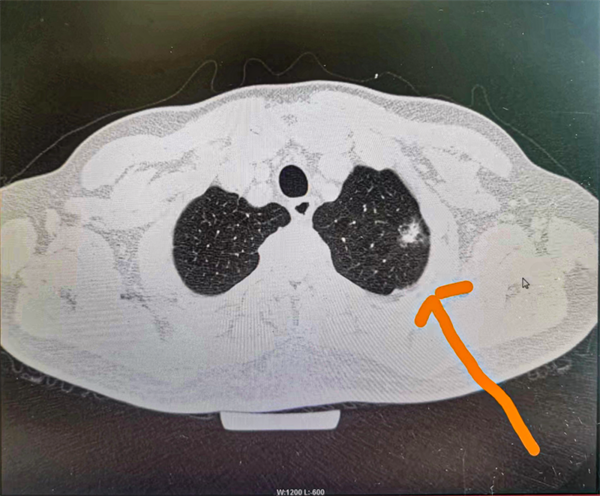

患者因10多天前不小心摔倒后一直说胸口痛,因此来院检查,发现左肺上叶有一个1.7cm左右的磨玻璃样结节,形态不规则,有分叶、毛刺等。普外、胸外科景锦主任立即组织开展病例讨论,对患者病情进行全面分析及评估,根据患者病史及各项辅助检查,并与患者及家属充分沟通征得同意后,决定行“胸腔镜下左肺上叶切除术+术中快速冰冻活检术”。在麻醉科的通力配合下顺利实施手术,术中先行左肺上叶病灶楔形切除后送快速冰冻检查后确认为浸润性肺腺癌,立即行左肺上叶切除术。术后第二天患者即下床活动。术后病理证实为浸润性肺腺癌。